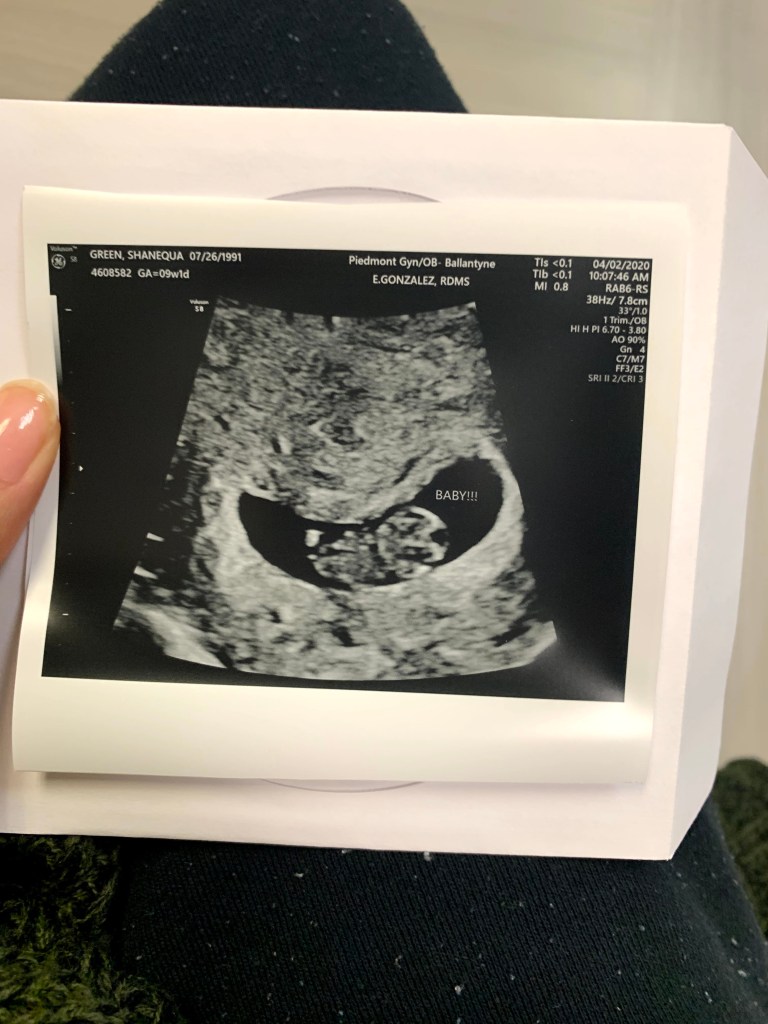

All in all, this first trimester was different this pregnancy, I was able to see the little one on the ultrasound, but my husband hasn’t been able to come with me to my appointment due to our governors stay-at-home orders. Everything looks healthy with this little bean.